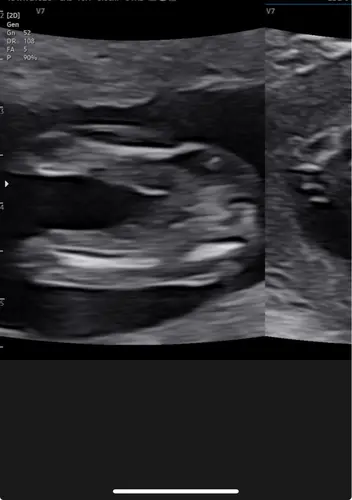

Hee dames ik ben 2 augustus uitgerekend en had de 13 weken pret echo. Ze zei dat het een jongetje wordt, maar bij m鈥檔 andere zoontje vondt ik met 13 weko het geslacht toch wat duidelijker.

Ik lees vaak dat ze het rond dit termijn toch fout hebben. Chat gtp zegt op basis van deze foto dat hij meer neigt naar een meisje omdat het ook niet omhoog staat ofzo en hij niet duidelijk balletjes en piemel ziet馃檲. Wat zouden jullie zeggen bij deze foto? Beide is voor ons meer dan welkom btw